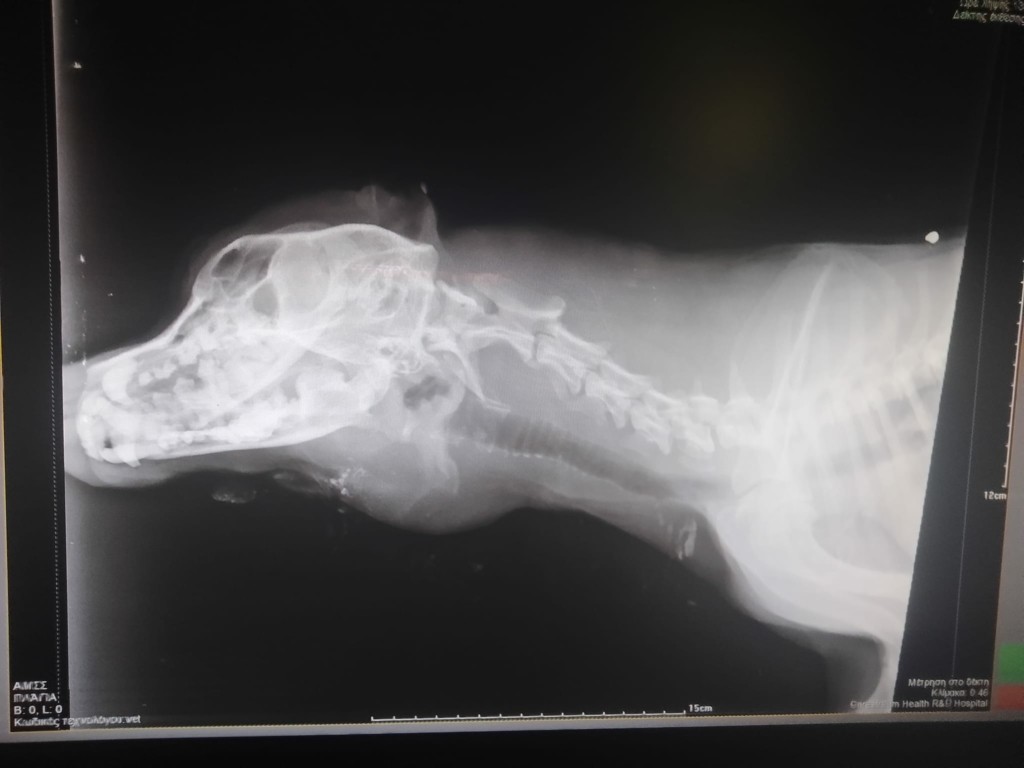

Το αδέσποτο σκυλάκι φαίνεται να έχει πυροβοληθεί τουλάχιστον δέκα φορές με αεροβόλο όπλο.

Το νέο περιστατικό κακοποίησης ζώων φέρνει στο φως ο Φιλοζωικός Σύλλογος Εμμανουήλ Παππά, αναφέροντας ότι ο Smiley, όπως ήταν το όνομά του, δέχθηκε τουλάχιστον 10 πυροβολισμούς από αεροβόλο όπλο που κρατούσε στα χέρια του ασυνείδητος κάτοικος του χωριού, με αποτέλεσμα να βρει φρικτό θάνατο.